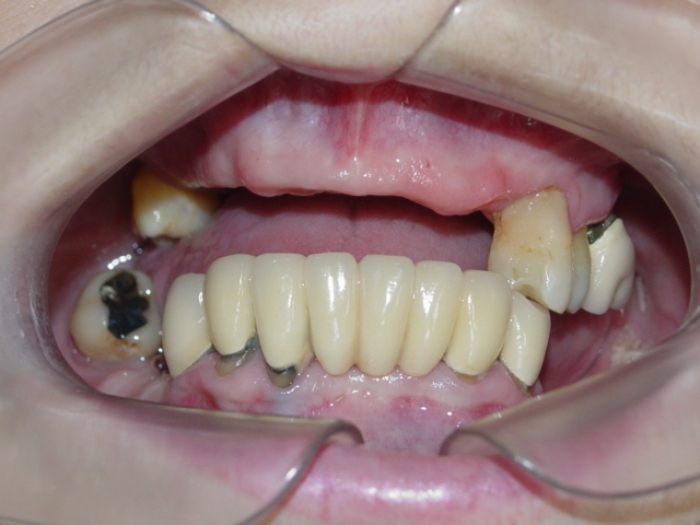

Imagens iniciais